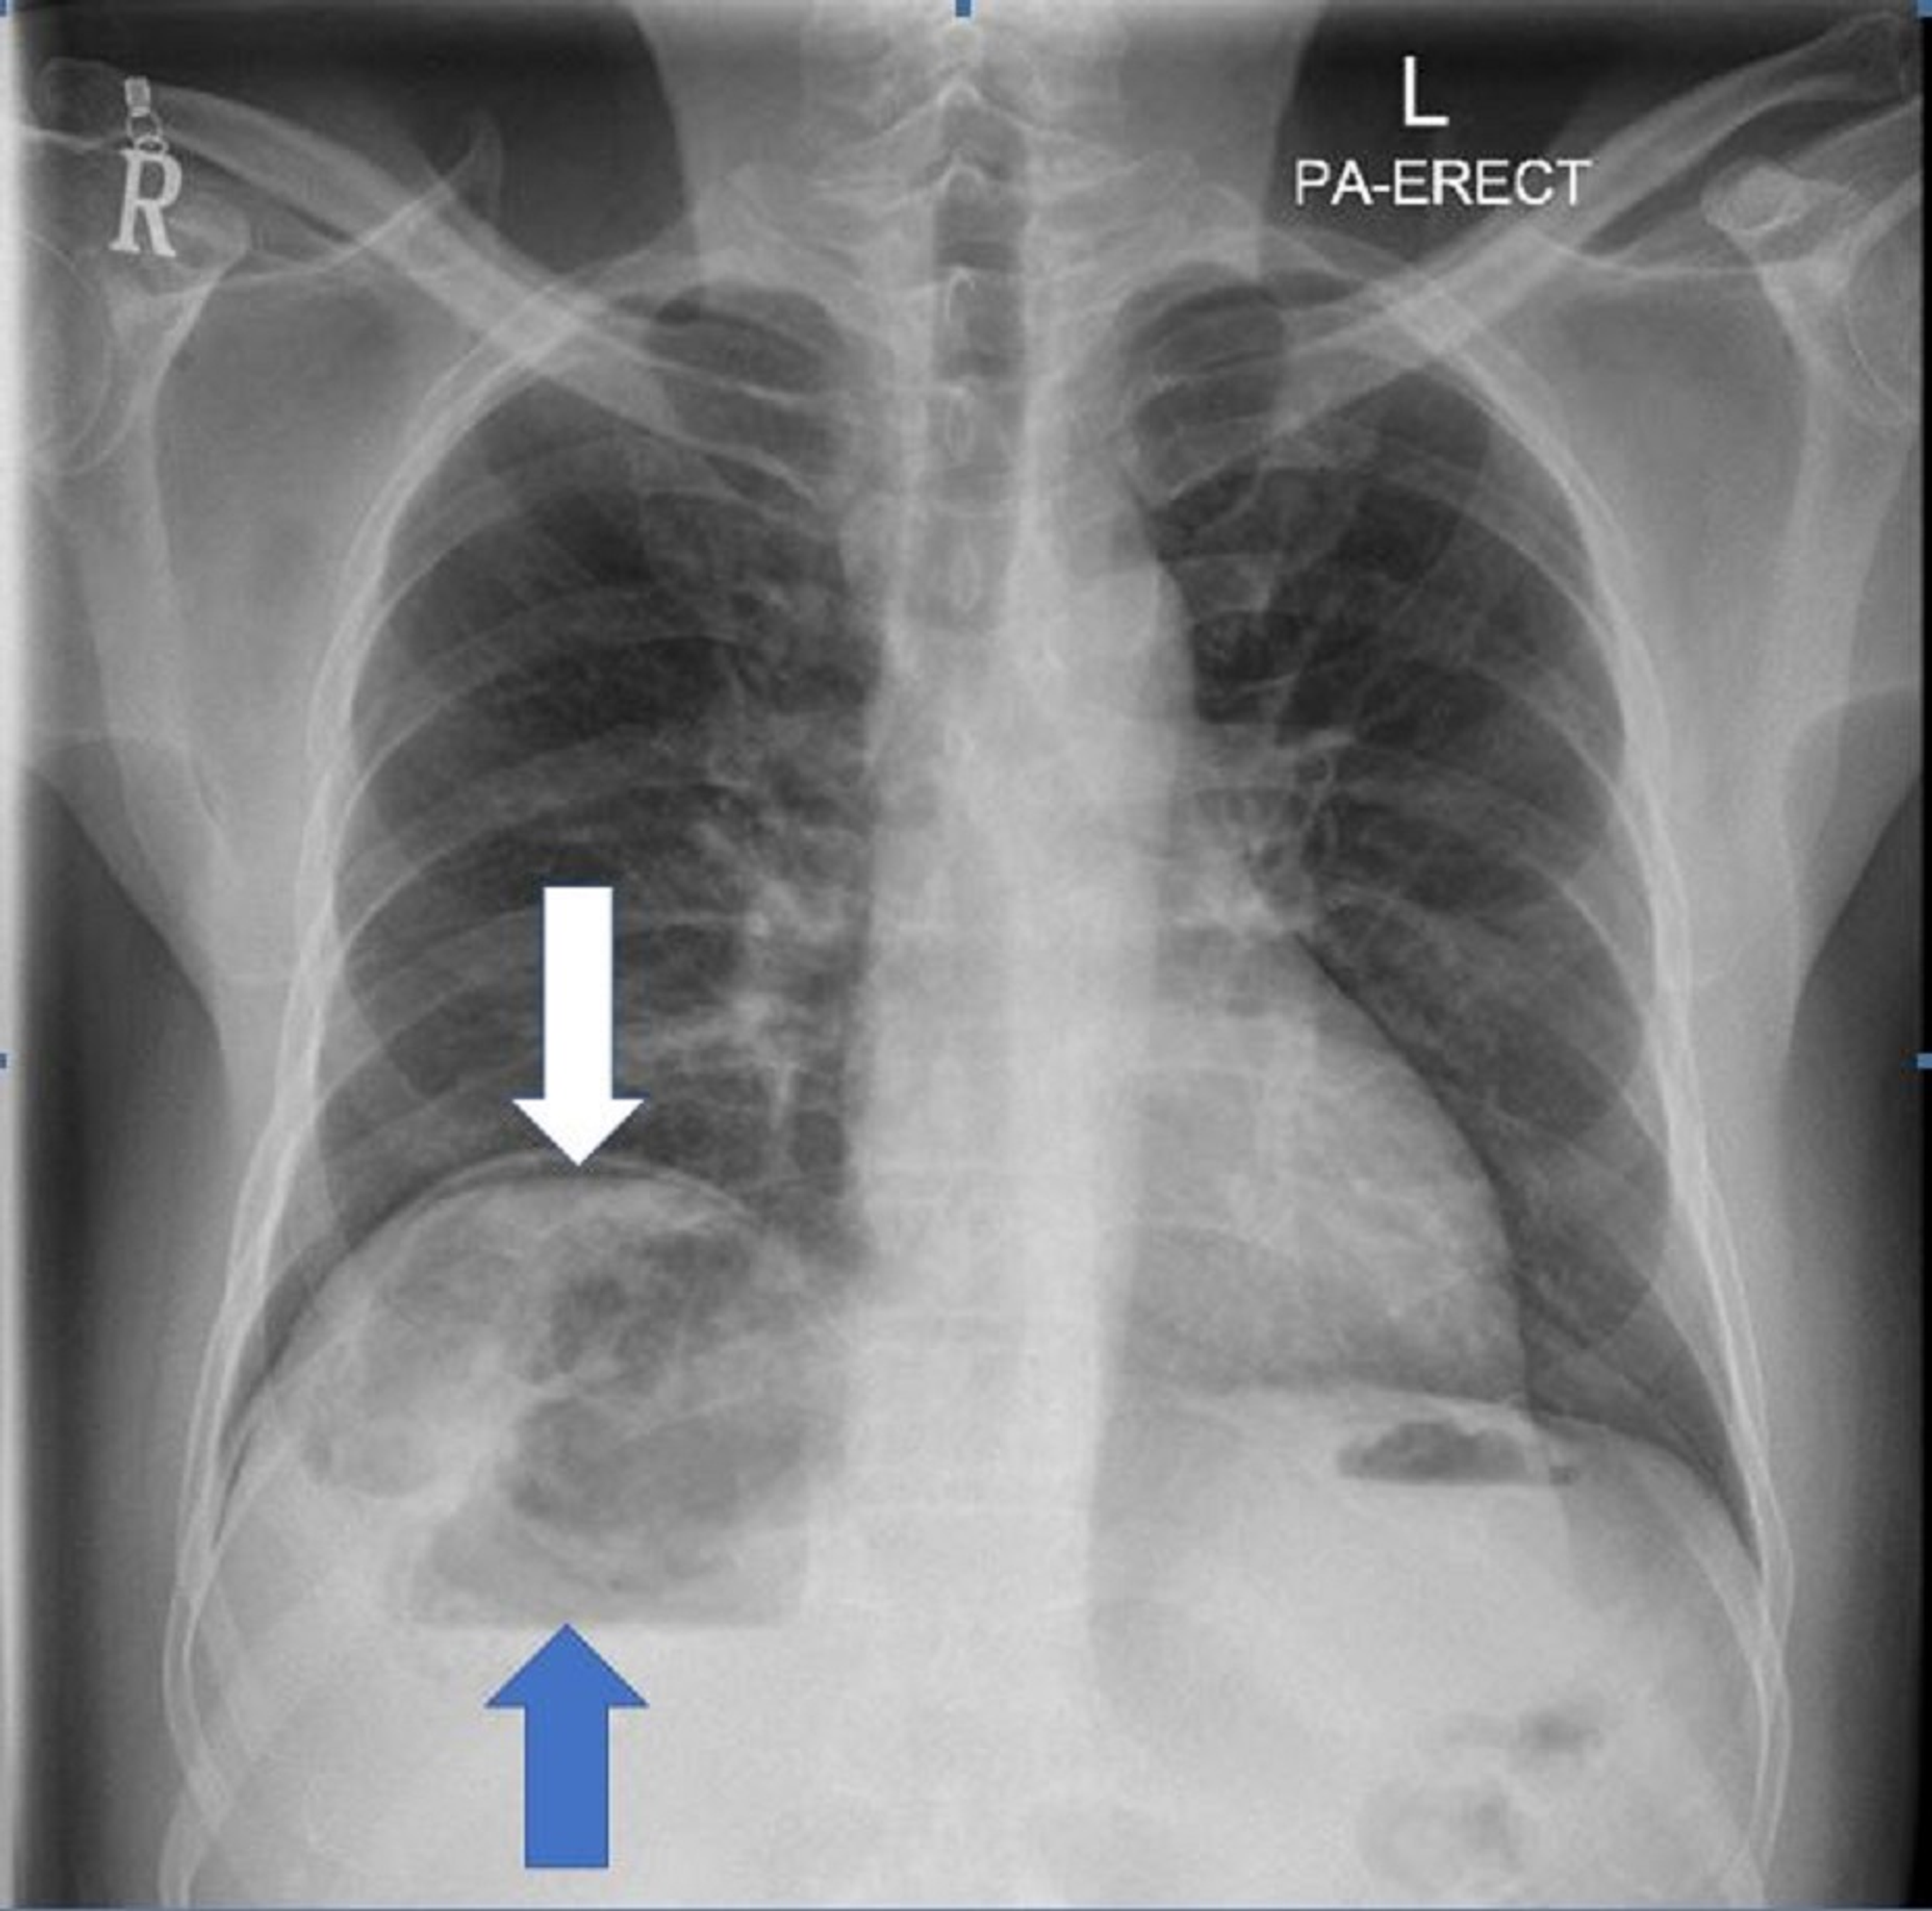

A Chest Radiograph showed a small air pocket in the paraspinal space Air Pocket In Liver Pneumobilia is usually characterized by the presence. It is typically the result of an abnormal communication. pneumobilia refers to the presence of air within the bile ducts, gallbladder, or liver. Pneumobilia usually can be distinguished from air in the portal venous system by its appearance on computed tomography (ct) scan. pneumobilia, or air within the biliary tree of. Air Pocket In Liver.